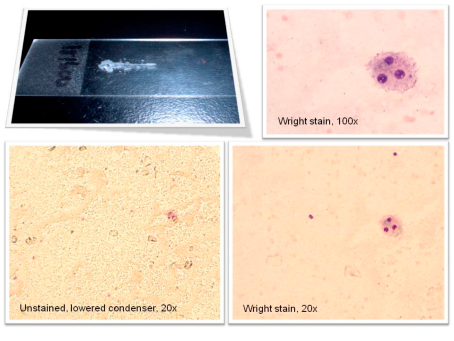

El estudio se realizó en dos fases. En la primera fase, se inyectó triamcinolona más solución de Ringer Lactato en la DIPJ de ambas extremidades anteriores de siete caballos. Se obtuvo el líquido sinovial de la bursa navicular a los 30 minutos y a una, tres, seis y nueve horas después de la inyección. Además, se evaluó este líquido para determinar en qué momento ocurrió la concentración más alta de triamcinolona. La concentración más alta de triamcinolona en la bursa navicular ocurrió seis horas después de la inyección en la DIPJ. En la segunda fase, se les inyecto a 11 caballos triamcinolona más solución de Ringer Lactato en una DIPJ de la extremidad anterior y una inyección de triamcinolona más ácido hialurónico en la otra extremidad anterior. Seis horas después de la inyección, se evaluó las muestras del líquido sinovial obtenidas de las bursas naviculares de las extremidades anteriores y posteriores de cada caballo. Las muestras de las extremidades posteriores sirvieron como un grupo de control sistémico ya que la absorción sistémica de la triamcinolona ocurre después de una inyección articular.

No se detectó triamcinolona en las muestras de la DIPJ previas a la inyección en los caballos de la segunda fase del estudio. Se encontró triamcinolona en todas las muestras de la bursa navicular de las extremidades posteriores después de la inyección y no se vio una diferencia significativa en las concentraciones de triamcinolona entre las extremidades anteriores que recibieron ácido hialurónico y aquellas que no. Se detectó una concentración significativamente mayor de triamcinolona en la bursa navicular de las extremidades anteriores que en la bursa navicular de las extremidades posteriores, lo cual representa un grado menor de absorción sistémica. La bursografía navicular realizada después de las inyecciones reveló que no existe ninguna comunicación directa entre la DIPJ y la bursa navicular. Aunque las concentraciones individuales de triamcinolona en el líquido sinovial variaron ampliamente, los resultados demuestran que la triamcinolona se difunde rápidamente entre la DIPJ y la bursa navicular de los caballos clínicamente normales y que la adición de una sustancia de alto peso molecular no afecta este movimiento. Estos resultados allanan el camino para nuevas investigaciones sobre los efectos, tanto positivos como negativos, del síndrome navicular en la permeabilidad de la membrana sinovial, la estructura de ácido hialurónico y el metabolismo de los fármacos en una articulación inflamada. Los profesionales de la veterinaria en equinos han sospechado desde hace tiempo que existe una relación, y ahora hay más datos que apoyan el tratamiento del síndrome navicular mediante inyecciones en la DIPJ.